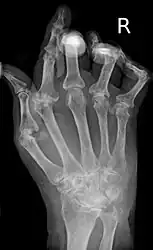

A hand severely affected by rheumatoid arthritis. This degree of swelling and deformation does not typically occur with current treatment.

As the pathology progresses the inflammatory activity leads to tendon tethering and erosion and destruction of the joint surface, which impairs range of movement and leads to deformity. The fingers may suffer from almost any deformity depending on which joints are most involved. Specific deformities, which also occur in osteoarthritis, include ulnar deviation, boutonniere deformity (also "buttonhole deformity", flexion of proximal interphalangeal joint and extension of distal interphalangeal joint of the hand), swan neck deformity (hyperextension at proximal interphalangeal joint and flexion at distal interphalangeal joint) and "Z-thumb." "Z-thumb" or "Z-deformity" consists of hyperextension of the interphalangeal joint, fixed flexion and subluxation of the metacarpophalangeal joint and gives a "Z" appearance to the thumb.[19]: 1098  The hammer toe deformity may be seen. In the worst case, joints are known as arthritis mutilans due to the mutilating nature of the deformities.[23]